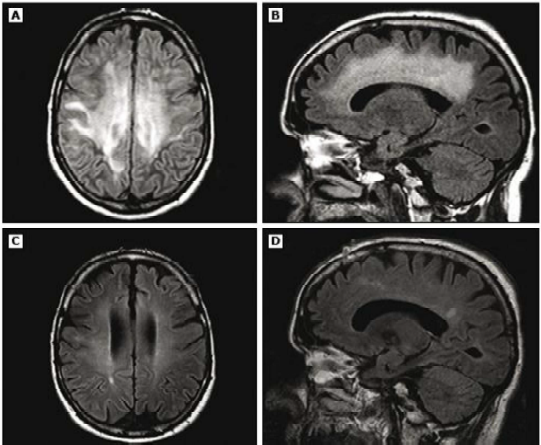

Paciente do sexo feminino, 22 anos, com quadro de cefaleia, mal-estar, confusão mental, febre não termometrada, meningismo, ataxia, afasia, nistagmo e retenção urinária.

Com base no caso clínico e nas imagens apresentadas, qual o provável diagnóstico?